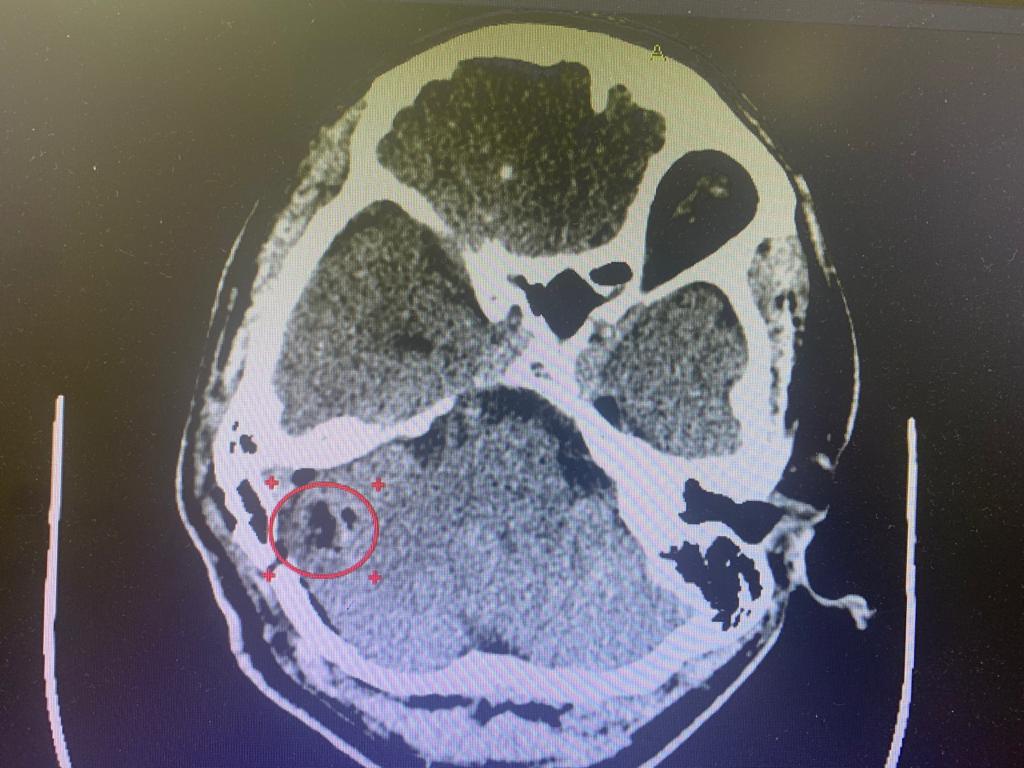

Были назначено полное обследование пациента. На МРТ головного мозга выявлена кавернома правого полушария мозжечка,  имелись признаки перенесённого кровоизлияния. Учитывая хирургическую доступность к каверноме, нейрохирурги клиники выполнили операцию, пациент при этом находился в положении сидя.

Кавернома удалена тотально.